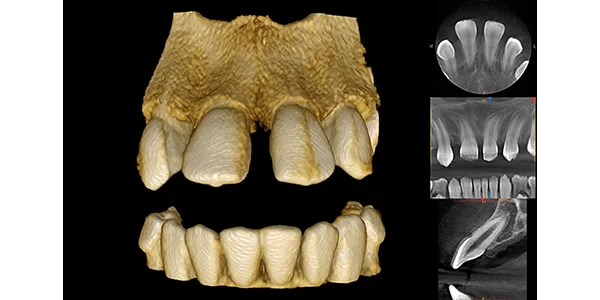

Cone Beam Computed Tomography (CBCT) is a unique type of X-Ray that allows a Dental Surgeon to see the Craniofacial structures, bone, soft tissues, and even nerve pathways of a patient, all in a 3D Image. Unlike Panoramic X-Rays which are 2 dimensional, the CBCT scan allows doctors to see buccal/Lingual distance, bone quality and surgically plan the placement of each implant.

The 3D CBCT X-Ray is not only useful in the surgical planning of Implants, but it is also helpful in detecting tumors and diagnosing Temporomandibular Joint Disorders (TMJ).